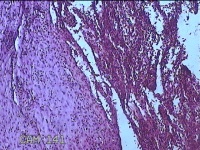

宫颈管组织

性别

女

年龄

33岁

临床诊断

异位妊娠

一般病史

停经52天,阴道流血12天。

标本名称

大体所见

灰白暗红色不规则碎组织4.3x3.3x1.2cm一堆。